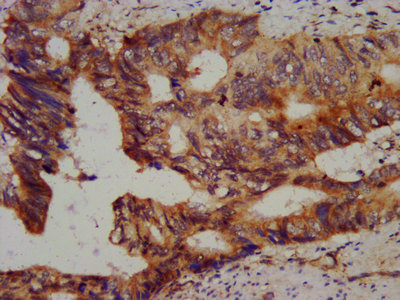

IHC image of CSB-PA878944LA01HU diluted at 1:800 and staining in paraffin-embedded human colon cancer performed on a Leica BondTM system. After dewaxing and hydration, antigen retrieval was mediated by high pressure in a citrate buffer (pH 6.0). Section was blocked with 10% normal goat serum 30min at RT. Then primary antibody (1% BSA) was incubated at 4°C overnight. The primary is detected by a biotinylated secondary antibody and visualized using an HRP conjugated SP system.